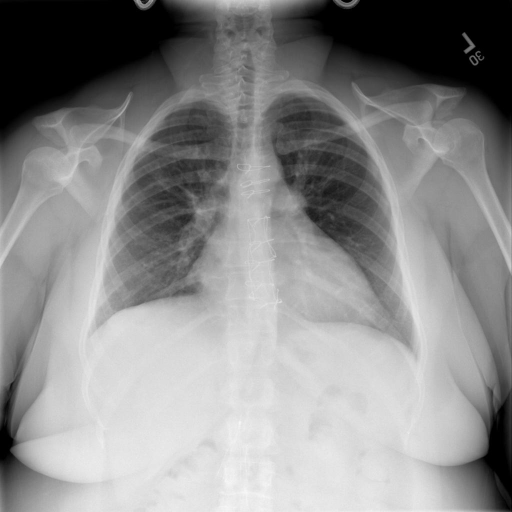

# 本文贡献  - 借助ChatGPT以及公开的数据集,我们构造了一个`X光影像-诊断报告`对的医学多模态数据集; # 数据集 - [MIMIC-CXR](https://physionet.org/content/mimic-cxr-jpg/2.0.0/)是一个公开可用的胸部X光片数据集,包括377,110张图像和227,827个相关报告。 - [OpenI](https://openi.nlm.nih.gov/faq#collection)是一个来自印第安纳大学医院的胸部X光片数据集,包括6,459张图像和3,955个报告。 在上述工作中,报告信息都为非结构化的,不利于科学研究。为了生成合理的医学报告,我们对两个数据集进行了预处理,并最终得到了可以用于训练的**英文报告**。除此之外,为了更好的支持中文社区发展,借助ChatGPT的能力,我们将英文报告进行了中文翻译,并最终形成了可用于训练的数据集。 |数据集|数量|下载链接| |:-|:-|:-| |MIMIC-CXR-zh|-|-| |OpenI-zh|6,423|[诊疗报告](./data/Xray/openi-zh.json) 、[X光影像](https://pan.baidu.com/s/13GBsDMKf6xBZBSHpoWH_EA?pwd=k9sh)| # 快速上手 1. 安装环境 ```bash # 安装依赖 pip install -r requirements.txt # 国内换源安装依赖 pip install -i https://mirrors.aliyun.com/pypi/simple/ -r requirements.txt ``` 此时默认会安装`deepspeed`库(支持`sat`库训练),此库对于模型推理并非必要,同时部分`Windows`环境安装此库时会遇到问题。 如果想绕过`deepspeed`安装,我们可以将命令改为: ```bash # 安装依赖 pip install -i https://mirrors.aliyun.com/pypi/simple/ -r requirements_wo_ds.txt # 安装SwissArmyTransformer pip install -i https://mirrors.aliyun.com/pypi/simple/ --no-deps "SwissArmyTransformer>=0.3.6" ``` 2. 模型推理 CLI推理: ```python python cli_demo.py --from_pretrained checkpoints/finetune-XrayGLM-05-25-01-04 --prompt_zh '详细描述这张X光影像' ``` 更多[参数](https://github.com/WangRongsheng/XrayGLM/blob/main/cli_demo.py#L16) # 效果展示 |X光影像|诊疗报告(医生)|XrayGLM| |:-|:-|:-| ||根据X射线图像,心脏大小正常,肺部看起来很清晰。已经排除了肺炎、积液、水肿、气胸、腺病、结节或肿块的存在。该发现表明一切正常。换句话说,总体印象是胸部正常。|X光片显示,心脏大小正常。肺部没有气胸或胸腔积液的证据。骨骼结构看起来没有任何异常。总的来说,X光片表明没有发现急性心肺疾病的迹象。| # 项目致谢 1. [VisualGLM-6B](https://github.com/THUDM/VisualGLM-6B)为我们提供了基础的代码参考和实现; 2. [MiniGPT-4](https://github.com/Vision-CAIR/MiniGPT-4)为我们这个项目提供了研发思路; 3. ChatGPT生成了高质量的中文版X光检查报告以支持XrayGLM训练; 4. [gpt_academic](https://github.com/binary-husky/gpt_academic)为文档翻译提供了多线程加速; 5. [MedCLIP](https://github.com/RyanWangZf/MedCLIP) 、[BLIP2](https://huggingface.co/docs/transformers/main/model_doc/blip-2) 、[XrayGPT](https://github.com/mbzuai-oryx/XrayGPT) 等工作也有重大的参考意义;  这项工作由[澳门理工大学应用科学学院](https://www.mpu.edu.mo/esca/zh/index.php)硕士生[王荣胜](https://github.com/WangRongsheng) 、[段耀菲](https://github.com/IsBaSO4) 、[李俊蓉](https://github.com/lijunrong0815)完成,同时这项工作受到[檀韬](https://scholar.google.com/citations?hl=zh-CN&user=lLg3WRkAAAAJ)副教授、[彭祥佑](http://www.patrickpang.net/)老师的帮助支持。 *特别鸣谢:[USTC-PhD Yongle Luo](https://github.com/kaixindelele) 提供了有3000美金的OpenAI账号,帮助我们完成大量的X光报告翻译工作 # 免责声明 本项目相关资源仅供学术研究之用,严禁用于商业用途。使用涉及第三方代码的部分时,请严格遵循相应的开源协议。模型生成的内容受模型计算、随机性和量化精度损失等因素影响,本项目无法对其准确性作出保证。即使本项目模型输出符合医学事实,也不能被用作实际医学诊断的依据。对于模型输出的任何内容,本项目不承担任何法律责任,亦不对因使用相关资源和输出结果而可能产生的任何损失承担责任。 # 项目引用 如果你使用了本项目的模型,数据或者代码,请声明引用: ```bash @misc{wang2023XrayGLM, title={XrayGLM: The first Chinese Medical Multimodal Model that Chest Radiographs Summarization}, author={Rongsheng Wang, Yaofei Duan, Junrong Li, Patrick Pang and Tao Tan}, year={2023}, publisher = {GitHub}, journal = {GitHub repository}, howpublished = {\url{https://github.com/WangRongsheng/XrayGLM}}, } ``` # 使用许可 此存储库遵循[CC BY-NC-SA](https://creativecommons.org/licenses/by-nc-sa/4.0/) ,请参阅许可条款。